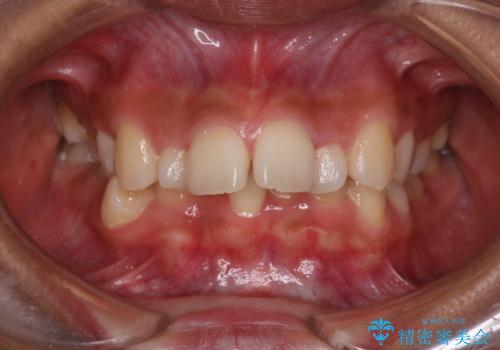

凸凹を綺麗にしたい。表側ワイヤー矯正

担当医 河口智英